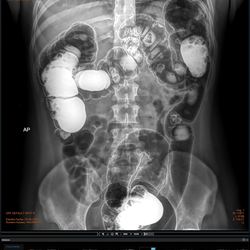

• Stitching automático con adquisición de hasta 4 imágenes.

Campo de visión de 17” X 17”

Colon 1

Urografía